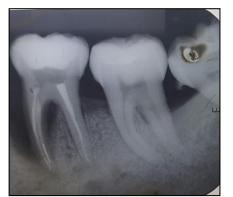

Observe a imagem a seguir:

Considere que o dente 46 possui uma coroa clínica com 9 mm de largura no sentido vestibulolingual; a sondagem horizontal da furca (vestibulolingual) foi de 6 mm; e, ainda, que havia uma parede óssea no lado lingual. É possível afirmar que, de acordo com a classificação de Hamp (1975), esse é um defeito de furca grau:

II.